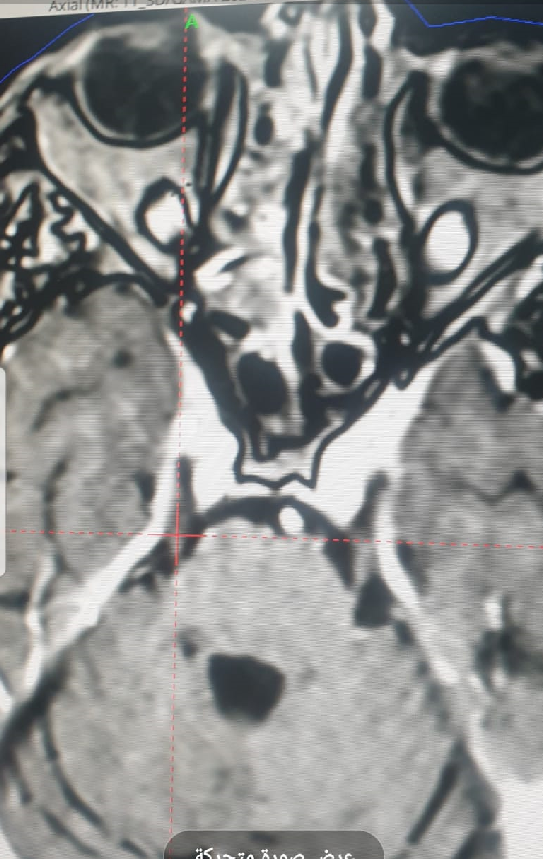

A trigeminal nerve tumor is treated with Gamma Knife radiation.

Professor Dr. Adil Ameer Jassim Mohammed, a faculty member in the Surgery Department at Al-Nahrain College of Medicine, treated a trigeminal nerve tumor using the latest technique, Gamma Knife radiation.